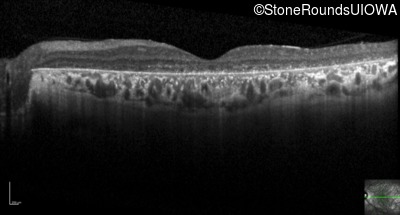

Optical Coherence Tomography - Left - 10/300 sc

Exemplar / OCT Stack

OCT Stack